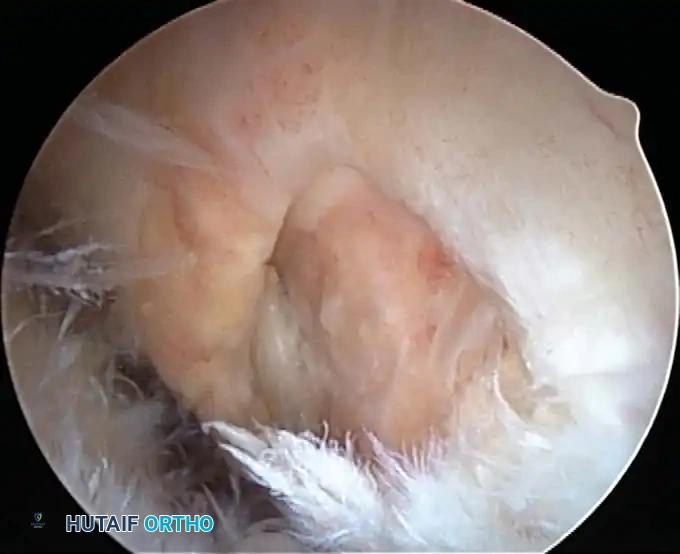

* Evaluation of primary rotator cuff impingement: Assessing the tissue quality of the rotator cuff to determine the feasibility of an all-arthroscopic repair versus an open or mini-open approach.

Once diagnostic evaluation is complete and hemostasis is secured, the therapeutic phase commences. Whether performing a SLAP repair, a Bankart stabilization, or a rotator cuff repair, the principles of tissue mobilization, anatomical footprint restoration, and secure biomechanical fixation remain paramount.

Modern arthroscopy relies heavily on suture anchors (biocomposite or all-suture constructs) and advanced arthroscopic knot-tying or knotless techniques. The ability to pass sutures through retracted, fibrotic tissue and secure them under appropriate tension without strangulating the microvascular supply is the hallmark of a master arthroscopist.